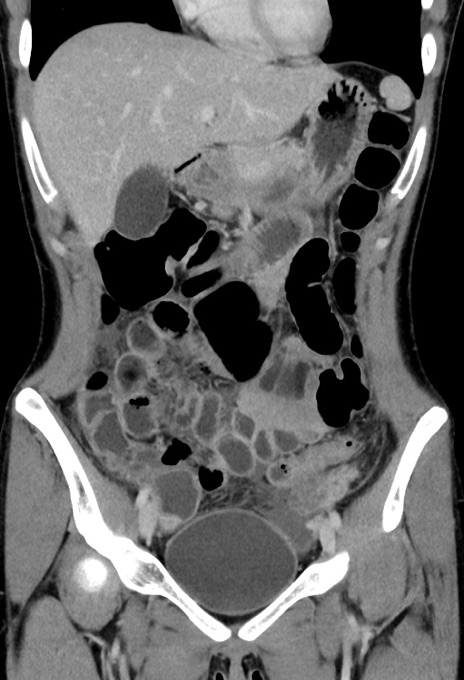

症例17(冠状断像)

【症例】20歳代女性

【主訴】嘔吐、下腹部痛

【現病歴】昨日夕食後に嘔吐し下腹部痛が出現。本日になっても嘔吐持続し改善しないため来院。

【身体所見】意識清明、BT 37.2℃、BP 108/67mmHg、腹部:平坦、やや硬、下腹部正中から右にかけて圧痛あり、反跳痛軽度あり、tapping pain(+)。

【データ】WBC 13600、CRP 14.94